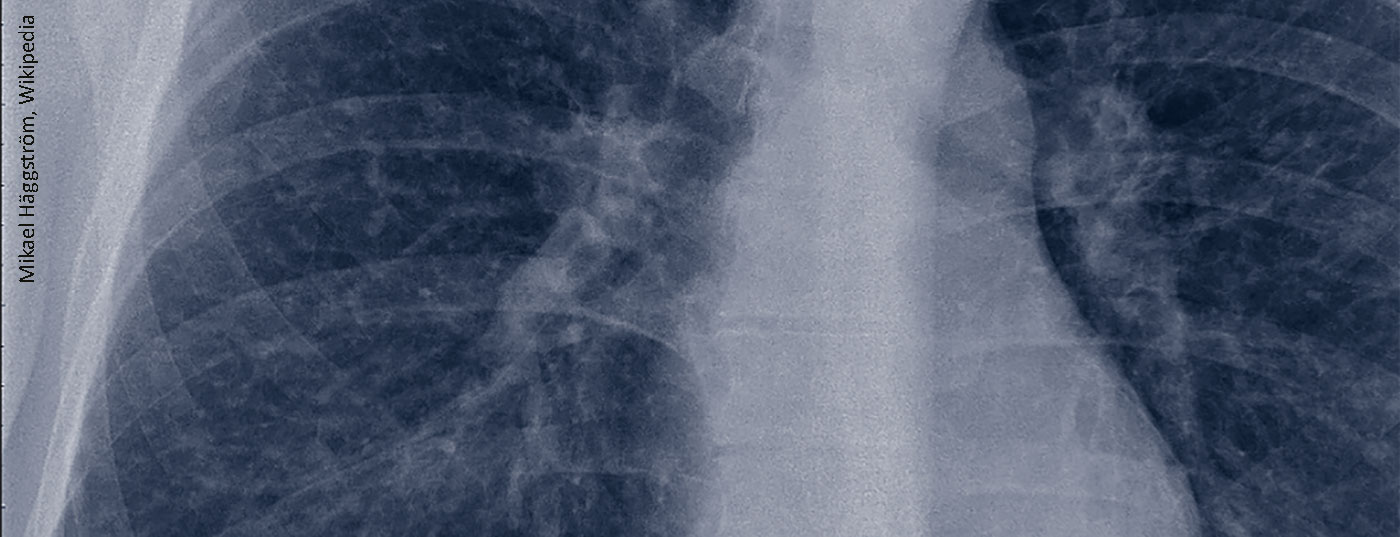

sarkoidose_lunge

Sarkoidose – ein Update für den Dermatologen

Diese heterogene Multisystemerkrankung mit immunvermitteltem Pathomechanismus weist in 20–30% der Fälle eine Hautbeteiligung auf, bei 60% sind weitere Organe betroffen. Neben einer histologischen Untersuchung ist ein Differenzialblutbild erforderlich für die Diagnosestellung. Das Spektrum therapeutischer Möglichkeiten reicht von topischen Glukokortikoiden oder Calcineurin-Antagonisten über Hydroxychloroquin bis zu Biologika.